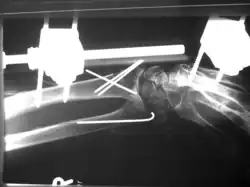

Aufgrund der Biegsamkeit der Drähte und der nicht formschlüssigen Verankerung der Drähte im Knochen ist das Operationsergebnis in der Regel nicht bewegungsstabil, sodass weitere Ruhigstellungsverfahren, z. B. Gipsverband oder auch der hier illustrierte Fixateur externe zur Anwendung kommen müssen.

Bei der hier dargestellten Handgelenkfraktur war eine bewegungsstabile Versorgung z. B. mittels winkelstabiler Platte (s. u.) aufgrund der hochgradigen Osteoporose und der erheblichen Weichteilschädigung nicht sinnvoll, daher erfolgte die geschlossene Reposition mit Kirschnerdraht-Fixierung und zusätzliche Ruhigstellung mit Fixateur externe. Eine Gipsruhigstellung wäre hier ebenfalls aufgrund der schlechten Weichteilverhältnisse nicht möglich gewesen.

Vorteil der Kirschnerdraht-Fixierung ist der geringe Verfahrensaufwand und die geringe Invasivität. Die Entfernung der Drähte erfolgt in der Regel unmittelbar nach Abschluss der Frakturheilung (also nach ca. 4 bis 6 Wochen).

Nachteil der Kirschnerdraht-Fixierung ist die Kombination der Risiken eines invasiven Eingriffes (Infektion, Narkoserisiko) mit den Nachteilen einer längeren Ruhigstellung (Muskelatrophie, Einsteifung des Gelenkes, keine frühfunktionelle Behandlung möglich).

Spezifische Komplikationen und Risiken sind „Wandern“ der Drähte, Drahtbruch und Korrekturverlust.